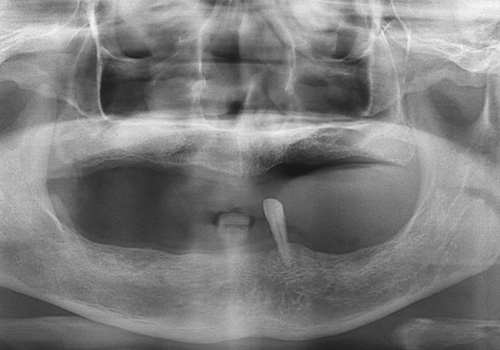

김○근님 임플란트 식립 전

2023년 2월